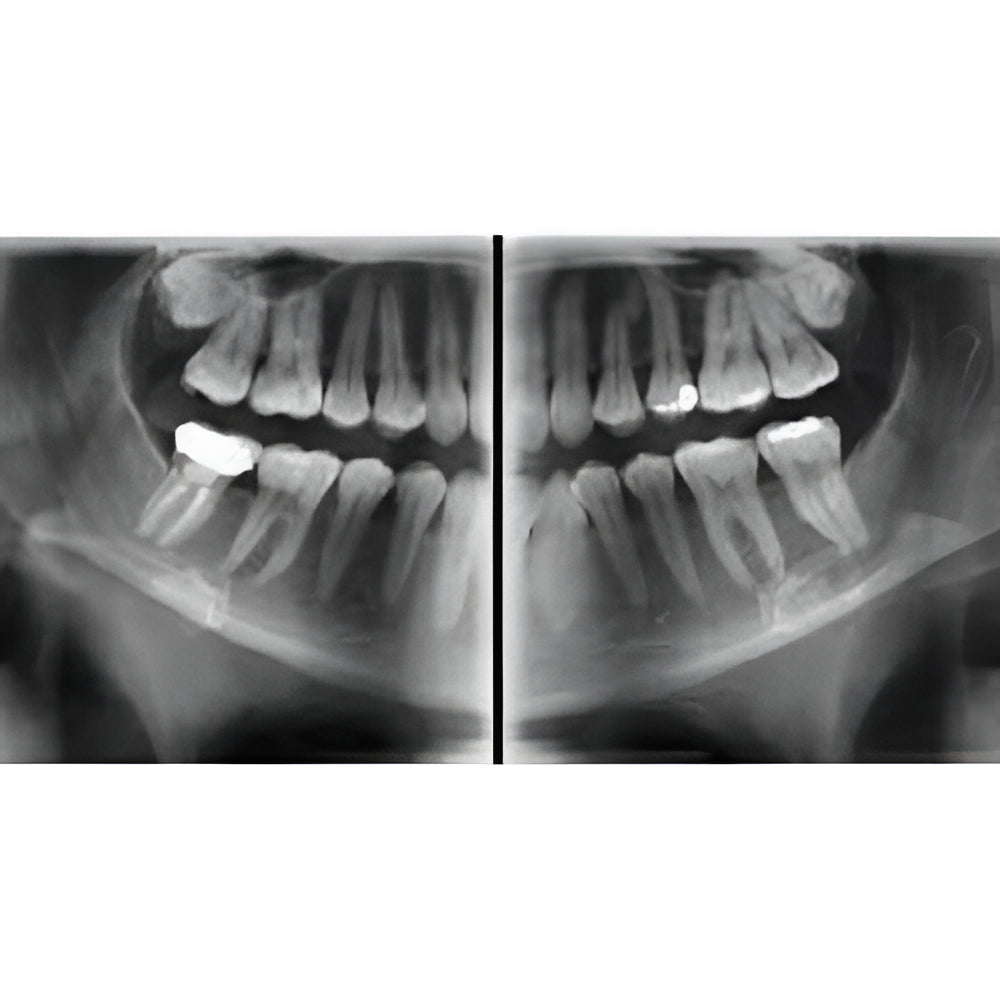

The Vatech PaX-i3D Green panoramic plus cone beam system delivers large field of view (up to 15 x 15 cm) dental CBCT scans in addition to standard 2D panorex and extraoral bitewing X-ray images. This Vatech CBCT machine features the innovative green CT technology which minimizes patient dose, while the Rapid Scan feature delivers high-quality 3D cone beam scans in just 5.9 seconds. A quick exposure time helps to minimize artifacts and motion, while at the same time reducing patient dose, making your imaging process more efficient and safer.

- Dedicated Panoramic

- Panoramic

- 3D Cone Beam

- Large FOV

- Multi-FOV

- Focused FOV

- Fast Scan Protocol

- Ultra Low Dose 3D

- Pedo Friendly

- Cephalometric

- Bitewing Program